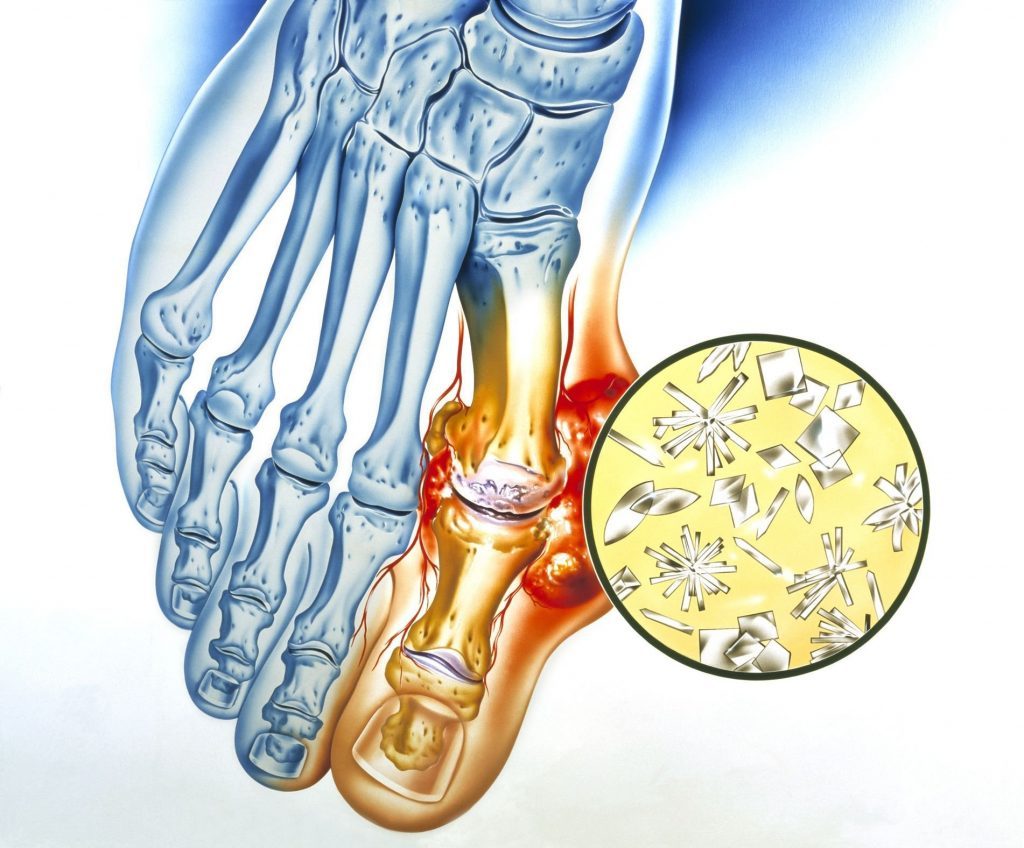

Combate à inflamação, ao inchaço articular e à sensação de “travamento” que muitas pessoas sentem na região da coluna.

Sentem dores nas articulações — joelhos, ombros, mãos — mas especialmente na coluna (lombar, cervical).